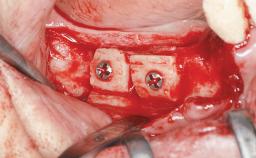

Bone Augmentation Horizontal|Staged|Vertical

Augmentation Materials Autogenous chips|Autogenous block(s)|Xenogenous

Bone Volume Deficient vertically or deficient vertically AND horizontally